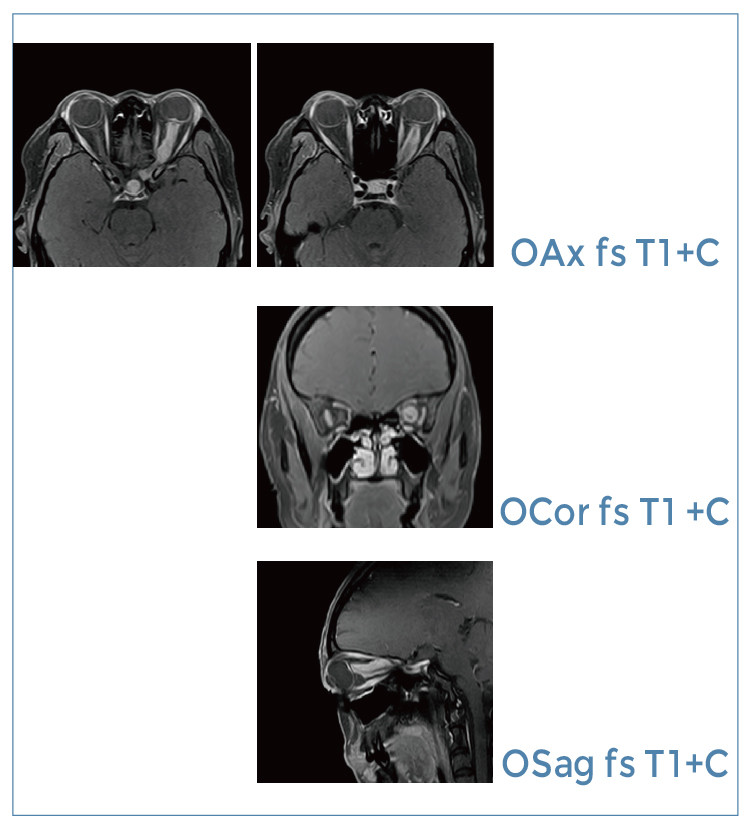

【朗润影像档案】磁共振影像病例分享(编号20191018)